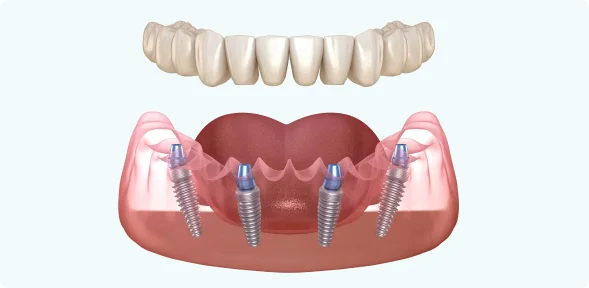

Для восстановления зубного ряда на одной челюсти используем всего четыре имплантата. Два устанавливаем вертикально в передней части челюсти. Еще два — под углом в боковом отделе, в местах с наибольшим объёмом костной ткани — это дает протезу надёжную опору. После установки имплантатов фиксируем несъёмный протез.

Для начала давайте разберёмся, что такое метод на 4-х имплантах и как выглядит данная конструкция.

Так будет выглядеть конструкция на нижней челюсти.

В конструкцию на 4-х имплантах входит:

- 4 Импланта

- 8 Коронок

Импланты устанавливаются в области 5-го зуба под углом, что позволяет избежать дорогостоящей операции по наращиванию костной ткани.